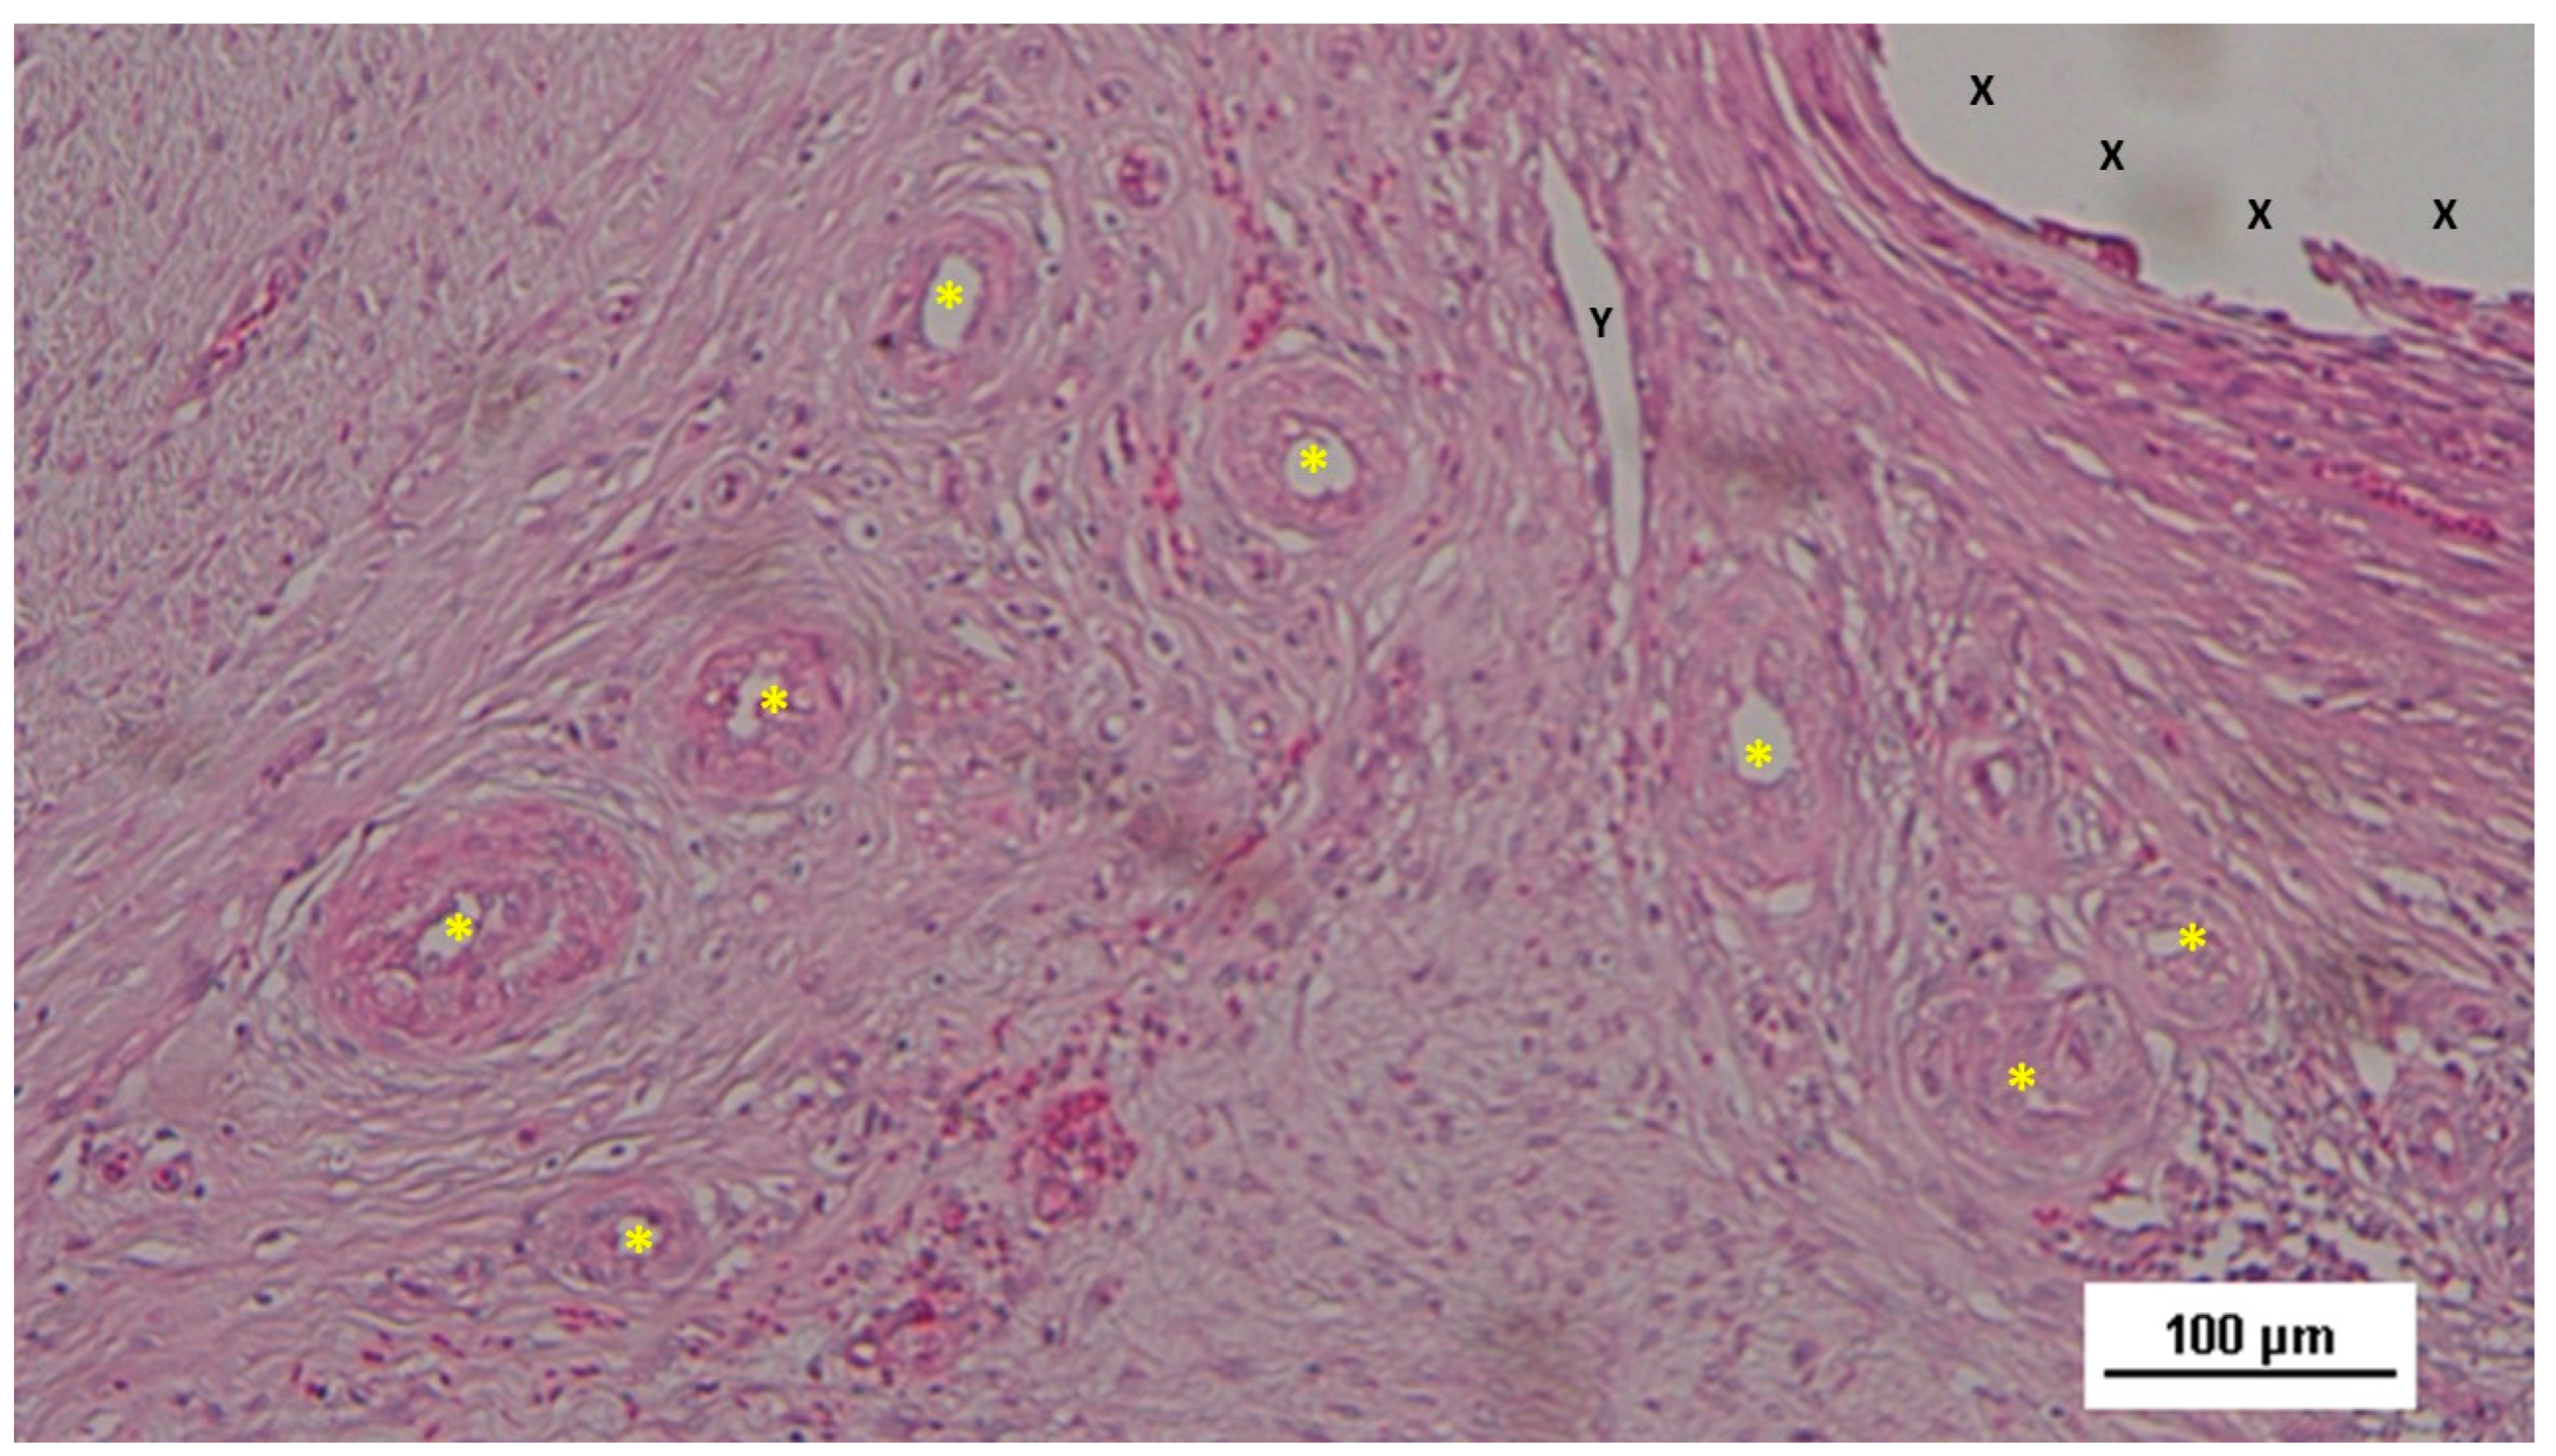

- Amato, G.; Puleio, R.; Romano, G.; Calò, P.G.; Di Buono, G.; Cicero, L.; Cassata, G.; Goetze, T.; Buscemi, S.; Agrusa, A.; et al. Physiologic Cyclical Load on Inguinal Hernia Scaffold ProFlor Turns Biological Response into Tissue Regeneration. Biology 2023, 12, 434. [Google Scholar] [CrossRef] [PubMed]

- Amato, G.; Romano, G.; Puleio, R.; Agrusa, A.; Goetze, T.; Gulotta, E.; Gordini, L.; Erdas, E.; Calò, P. Neomyogenesis in 3D Dynamic Responsive Prosthesis for Inguinal Hernia Repair. Artif Organs. 2018, 42, 1216–1223. [Google Scholar] [CrossRef]

- Amato G, Agrusa A, Puleio R, Calò PG, Goetze T, Romano G Neo-nervegenesis in 3D dynamic responsive implant for inguinal hernia repair. Qualitative study. International Journal of Surgery 2020, 76, 114–119. [Google Scholar]

- Amato, G.; Puleio, R.; Rodolico, V.; Agrusa, A.; Calò, P.G.; Di Buono, G. Romano G, Goetze T. Enhanced angiogenesis in the 3D dynamic responsive implant for inguinal hernia repair ProFlor®. Artif Organs. 2021, 00, 1–10. [Google Scholar]

- Amato G, Agrusa, Puleio R, Micci G, Cassata G, Cicero L, Di Buono G, Calò PG, Galia M, Romano G. A regenerative scaffold for inguinal hernia repair. MR imaging and histological cross evidence. Qualitative study. Int J Surg. 2021, 96, 106170. [Google Scholar]